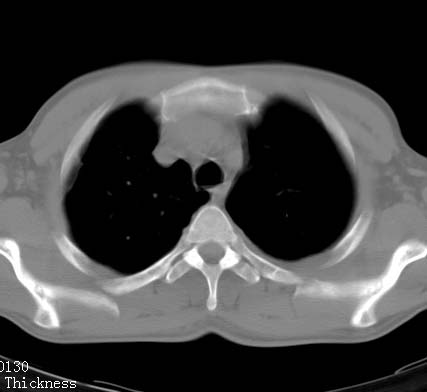

标题: CT10145:男性,30岁,活动后气促2月余.隔疝伴胸腔积液.右上肺结 [打印本页]

男性 病人 30岁,活动后气促2月余.隔疝伴胸腔积液.右上肺结核!

双肺上结核;膈肌裂孔疝。

左侧胸腔积液,并胸腔内见多个含液 气组织,并相互重叠。影像特征很特殊,应该是“膈疝”。支持!

左侧膈疝,及左侧胸水,双上肺结核。